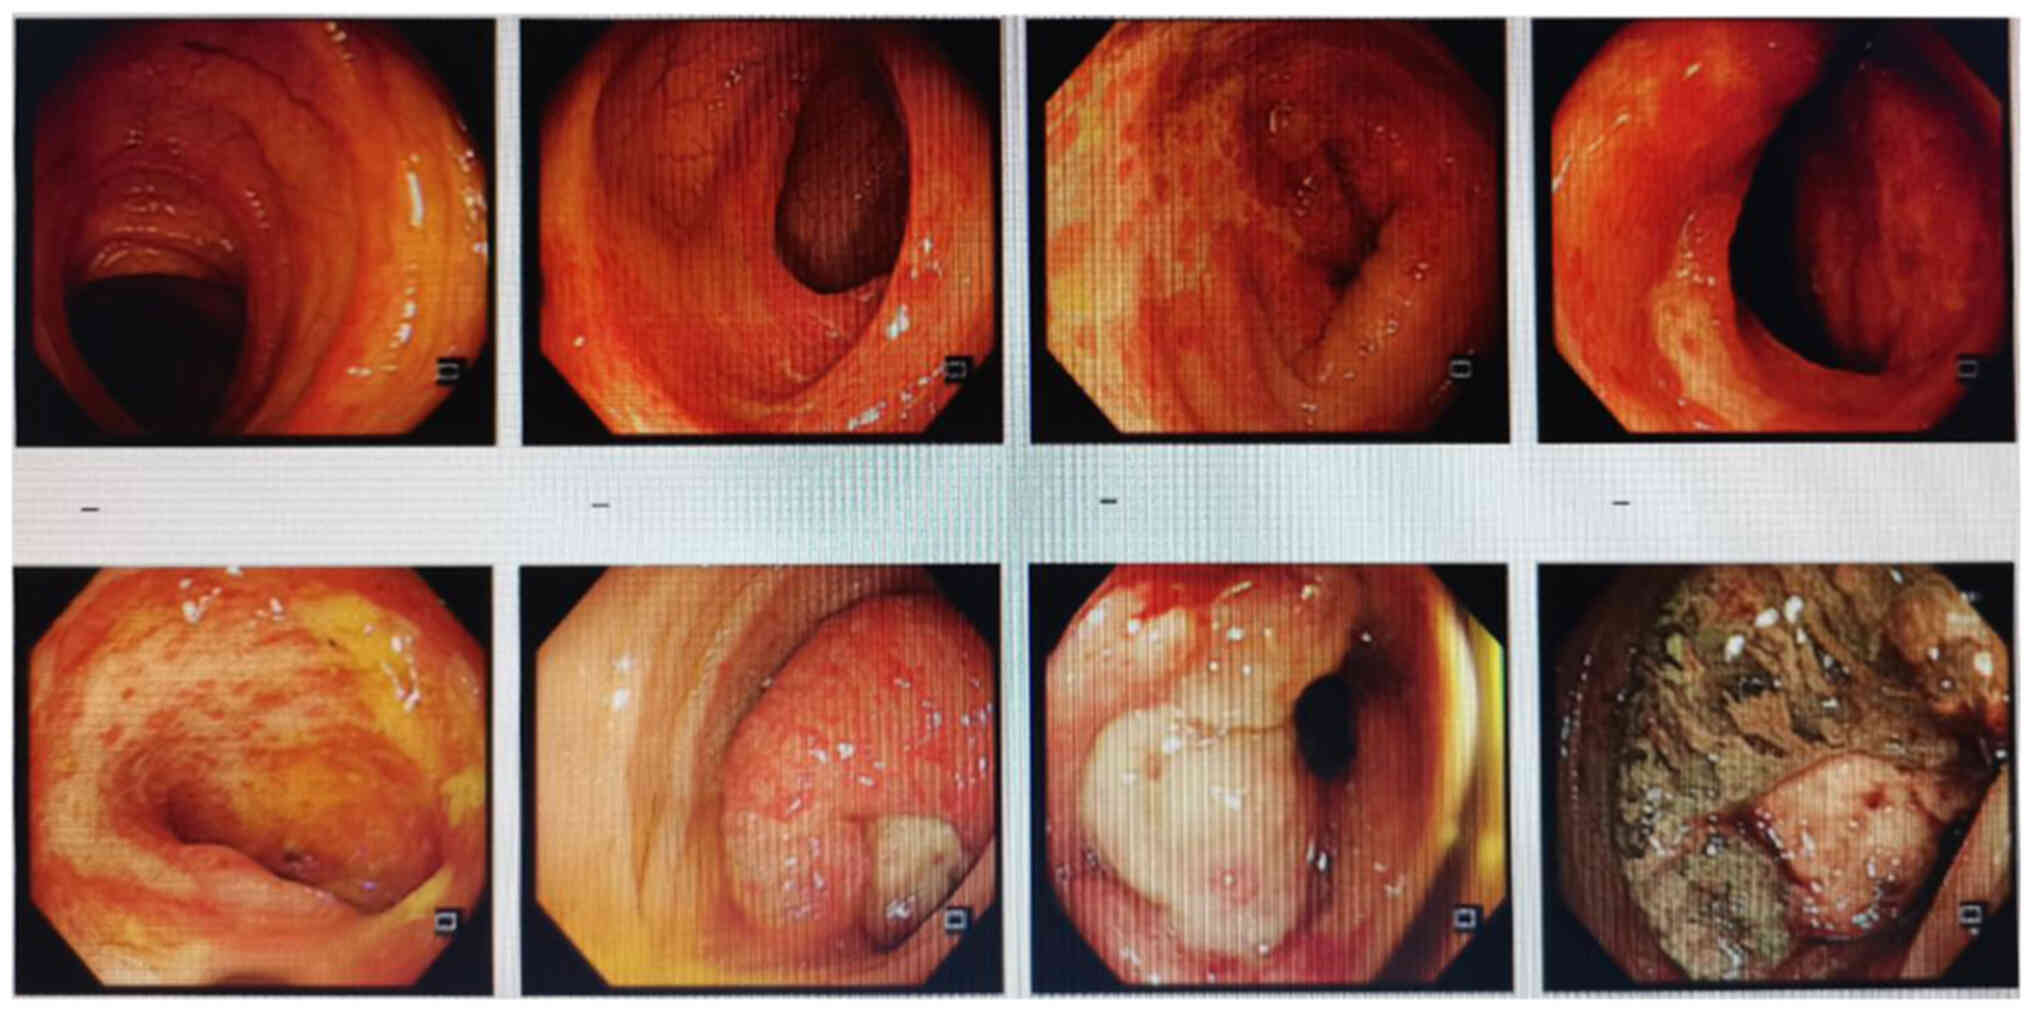

Initial assessment of the liver

lesions by magnetic resonance imaging on October 20, 2023. (A-C)

Metastases in the S2, S3 and S4 segments and (D) two enlarged lymph

nodes, one anterior and one posterior to the portal vein are shown.

Lesions are indicated by arrows.

Figure 3.

Initial assessment of the liver lesions by magnetic resonance imaging on October 20, 2023. (A-C) Metastases in the S2, S3 and S4 segments and (D) two enlarged lymph nodes, one anterior and one posterior to the portal vein are shown. Lesions are indicated by arrows.